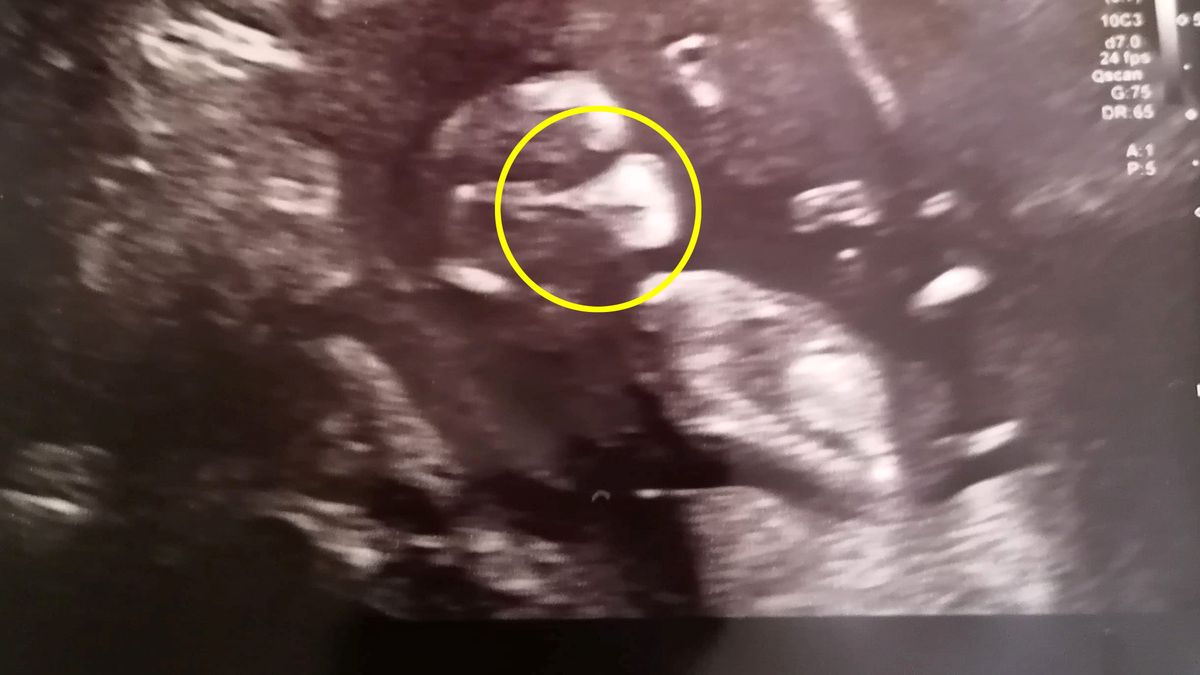

34-letnia kobieta przyznaje, że poczuła się oszołomiona, gdy podczas badania USG zobaczyła obraz swojego nienarodzonego dziecka. 12-tygodniowy bobas wygląda na nim, jakby był w maseczce. Co najciekawsze, kilka dni później kobieta uzyskała pozytywny wynik testu na koronawirusa. Pomyślała wtedy, że ​​obraz na badaniu był "znakiem".

Samantha Spicer z Rushden w Anglii początkowo bardzo się zdenerwowała, widząc na obrazie podczas badania USG wielki cień pokrywający nos i usta jej nienarodzonego dziecka. 12-tygodniowa córeczka Samanthy wydawała się być na nagraniu całkowicie świadoma tego, co się wokół niej dzieje. A cień na buzi dziecka wyglądał, jakby dziecko miało maseczkę.

Historia stała się jeszcze dziwniejsza, kiedy kilka dni później, Samantha uzyskała pozytywny wynik testu na obecność COVID-19. Wtedy kobieta stwierdziła, że choć zdjęcie początkowo wydawało się zabawnym zbiegiem okoliczności, nagle nabrało dużo głębszego znaczenia. Samantha dodała, że poczuła się, jakby dostała "znak" od córeczki, że ​​obie będą bezpieczne.

To bardzo niepewny czas, ale jesteśmy nastawieni pozytywnie, a to USG naprawdę nas rozśmieszyło. Przynajmniej wiemy, że jest przygotowana na życie w czasach koronawirusa - mówi rozbawiona 34-latka.